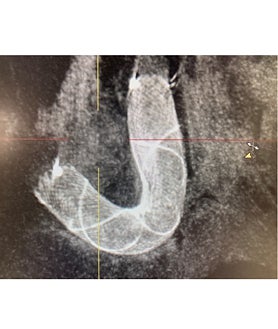

Se trataba de una paciente de 62 años con un aneurisma cerebral congénito con riesgo de sangrado en el que era precisa la implantación de un stent diversor de flujo para conseguir un cierre eficaz y seguro de la lesión. Según el doctor José Carlos Méndez, estas lesiones pueden asociar hasta un 10% de riesgo anual de hemorragia cerebral si no se detectan y se tratan a tiempo. «El tratamiento se realizó hace pocos días con el novedoso equipo de angiografía biplano instalado en el área quirúrgica del hospital», subraya el doctor.

En el caso concreto de esta paciente, tal y como explica el doctor Méndez, «era necesario disponer de la tecnología de imagen más avanzada para visualizar adecuadamente en 3D la lesión cerebral, debido a su complejidad anatómica». «Estos stents permiten el tratamiento del aneurisma sin manipular el mismo, ya que se implantan en la arteria donde asienta la lesión y condicionan cambio de flujo y trombosis del aneurisma, lo que minimiza los riesgos de la intervención», señala el doctor Vega.